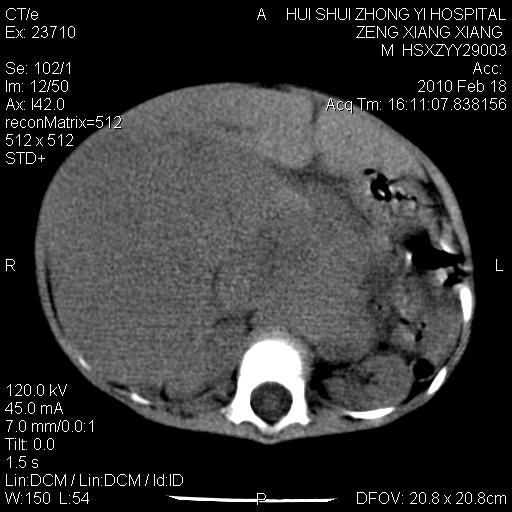

标题: PED3106:男,2岁,腹胀1月。 [打印本页]

标题: PED3106:男,2岁,腹胀1月。

定位腹膜后,肾上腺来源;

定性:恶性神经源性,肾上腺神经节母细胞瘤可能性大。

鉴别:肝母、肾母、肝脏中胚层错构瘤。

依据:年龄、有钙化,肾脏及肝脏受压移位。

肝母细胞瘤可能性大,右肾形态大体可见,不支持肾母细胞瘤,右肾移位不明显,肾上腺神经母细胞瘤可能性不大。